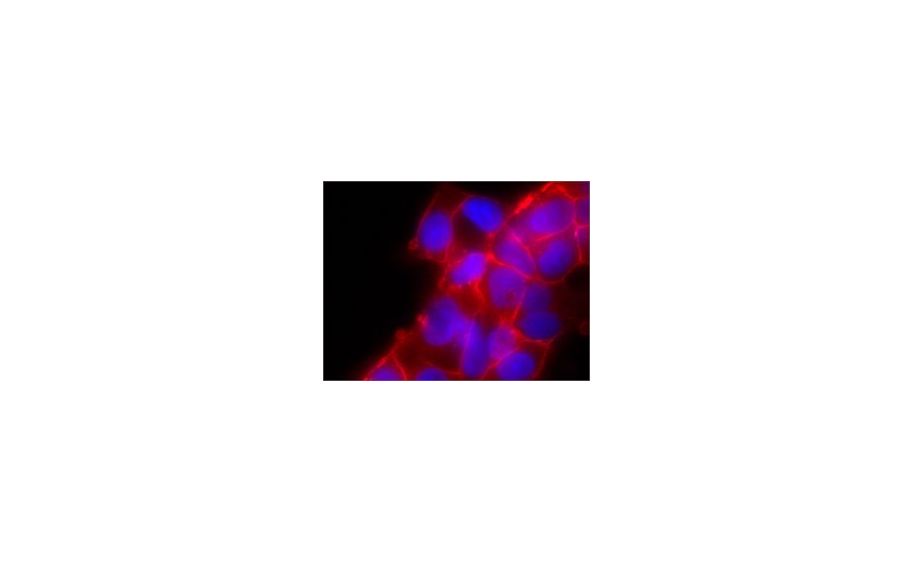

Monoclonal Anti-JAM-A antibody produced in mouse~1.0 mg/mL, clone J10.4, purified immunoglobulin

Monoclonal Anti-JAM-A antibody produced in mouse~1.0 mg/mL, clone J10.4, purified immunoglobulin